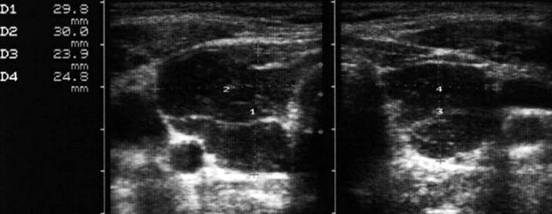

Femeie de 29 ani. Linfonodul in regiunea

laterocervicala dreapta ( 7x12x23mm, 1 cc) in neoplazie papilara a tiroidei. Structura

parenchimatoasa, neomogenea, cu margini

nete, cu absenta hilului.Examen citologic: metastaza de neoplazie papilara.

Lob drept,

proiectie trasversala si longitudinala

Aceeasi pacienta. Nodul de consistenta dura in lobul

drept spre istm.

Ecografia: nodul cu margini indistinte care deformeaza marginea anterioara a glandei,

parenchimatoasa, neomogena, hipoecogena. Prezenta de linfonodi laterocervicali.

Ctoaspiratie: carcinom papilar.